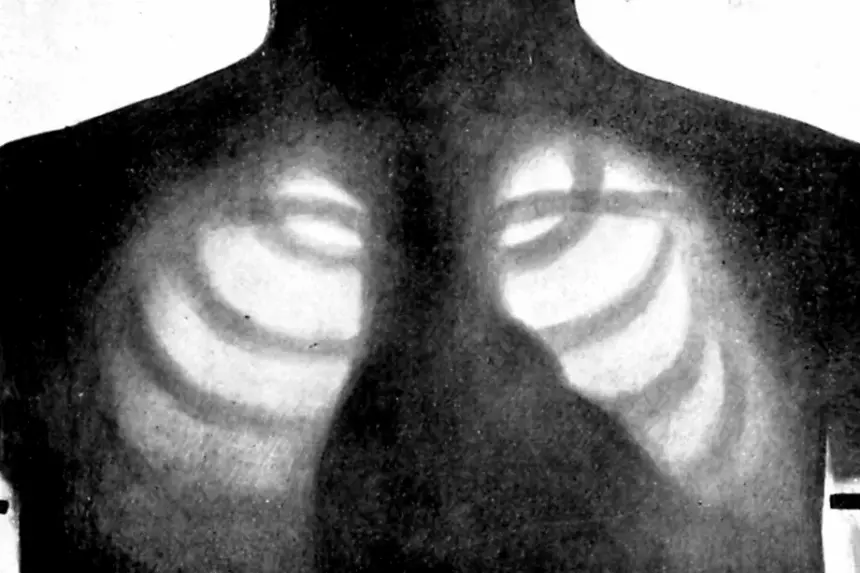

В Европейском союзе одобрили ПО на основе системы искусственного интеллекта, которое само делает рентген грудной клетки без участия рентгенолога. Отмечается, что первый полностью автономный ИИ для получения медицинских изображений.

Инструмент под названием ChestLink сканирует рентгеновские снимки грудной клетки и автоматически отправляет отчёты по пациентам, которых считает полностью здоровыми. Любые изображения, которые инструмент помечает как проблемные, отправляются рентгенологу для проверки. Как отмечают авторы проекта, большинство рентгеновских снимков не показывают никаких проблем, поэтому автоматизация процесса может сократить нагрузку на рентгенологов.